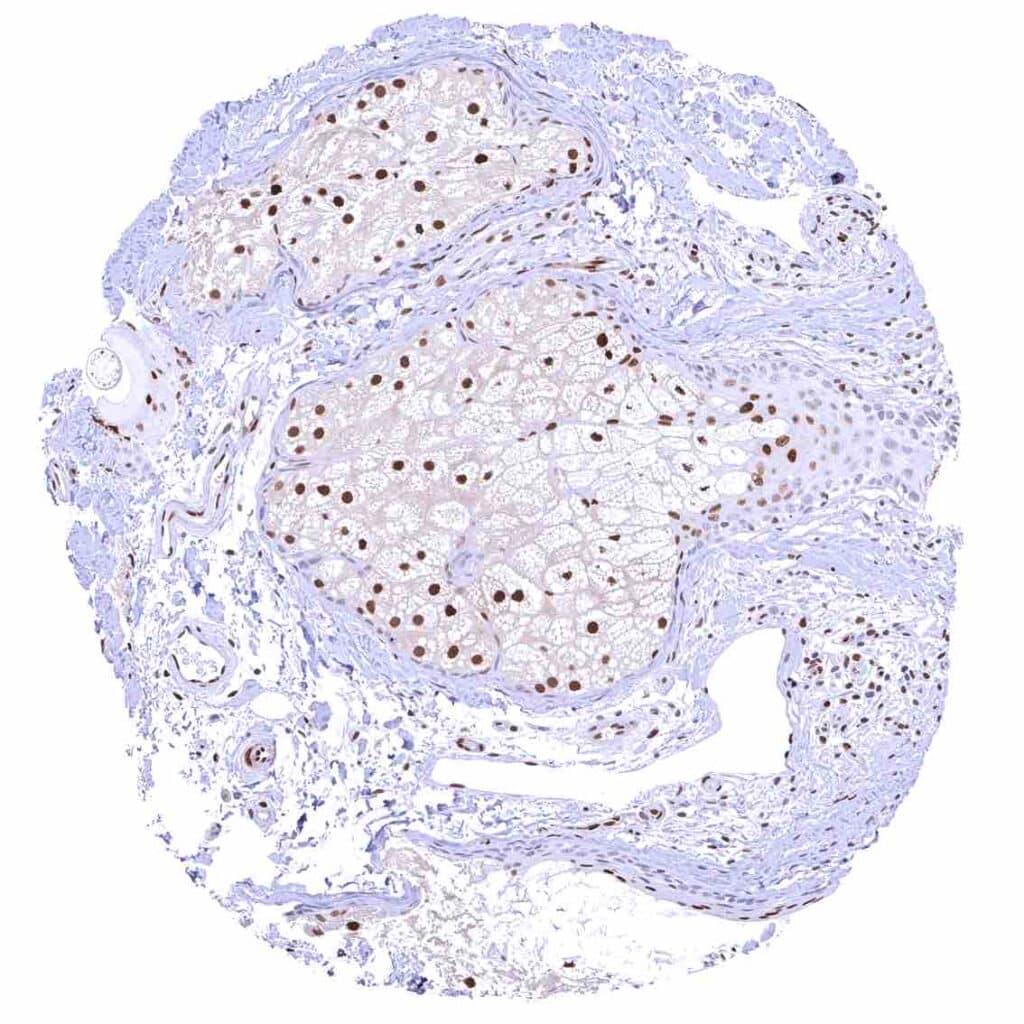

Testis – Weak to moderate nuclear p27 staining of a subset of cells (predominantly Sertoli cells).